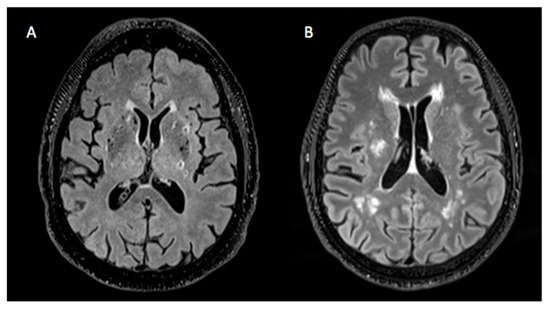

2.3. MRI Analysis